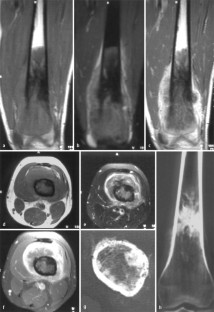

MRI morphology of bone tumors and tumor-like lesions

Für das Staging und die Charakterisierung von Knochentumoren und tumorähnlichen Läsionen ist in der Magnetresonanztomographie (MRT) der Einsatz von Spinechosequenzen erforderlich. Die MRT hat nur einen geringen Stellenwert in der Bestimmung der Dignität. Obwohl viele Knochentumoren und tumorähnliche Läsionen eine vergleichbare Morphologie in dieser bildgebenden Modalität aufweisen, können einige Tumorentitäten mittels MRT recht zuverlässig diagnostiziert werden. Hierzu zählen Knorpeltumoren, die solitäre und aneurysmatische Knochenzyste, der Riesenzelltumor, fetthaltige Läsionen und bis zu einem gewissen Grad auch das Osteoidosteom und das Osteoblastom. Es werden praktische Tipps gegeben, wann bei Tumorverdacht die MRT eingesetzt werden sollte, wie bei einem zufällig bei einer MRT gefundenen Tumor die Untersuchung modifiziert werden sollte und welcher Tumor vorliegen könnte.

Spin-echo sequences are mandatory at MRI for staging and characterization of bone tumors and tumor-like lesions. MRI is of minor value in the estimation of the malignant potential of an osseous lesion. Although many bone tumors and tumor-like lesions present similar morphology at MRI, some entities can be diagnosed with good reliability. These include chondrogenic tumors, solitary and aneurysmal bone cysts, giant cell tumors, lesions containing fatty tissue and, to a certain extent, osteoid-osteomas and osteoblastomas. Practical advice is given regarding when to perform a MRI study in cases of tumor suspicion. Further advices are given for cases a tumor is found incidentally at a MRI study, how to modify the study and which kind of tumor may be present.